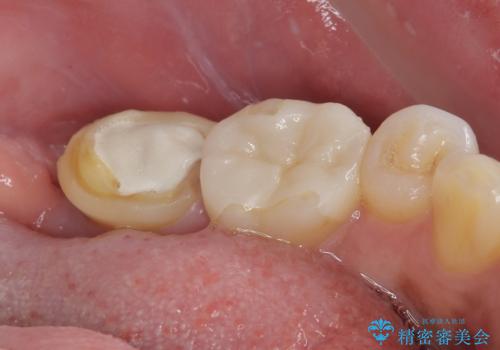

抜歯と同時にインプラントを埋入し、さらにその日のうちに仮歯を装着することで、見た目と機能を即日に回復しています。

従来のインプラント治療では、抜歯からインプラント埋入まで数か月の待機期間が必要でしたが、抜歯即時インプラントでは1回の外科処置で治療が完了するため、

・治療期間の短縮

・外科的侵襲(手術回数)の軽減

・患者さんの心理的・身体的負担の軽減

が可能です。